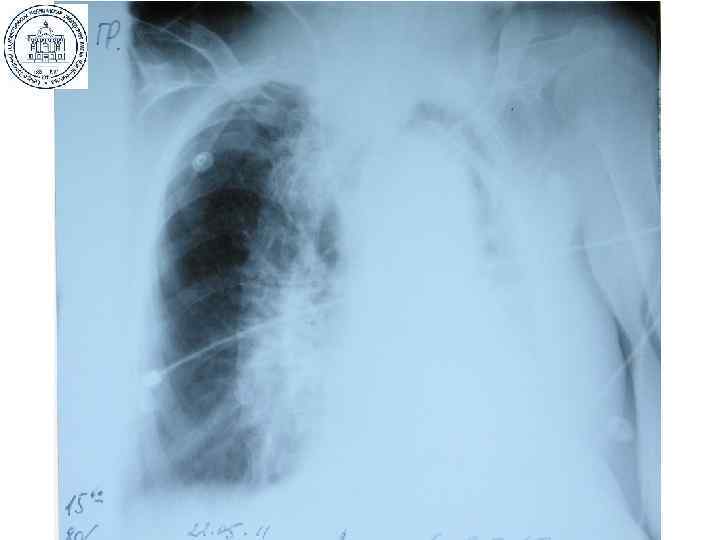

РIP 20 см, РЕЕР 10 см, F 12 мин-1, I: E 2: 1, FIO 2 1, 0

РIP 20 см, РЕЕР 10 см, F 12 мин-1, I: E 2: 1, FIO 2 1, 0